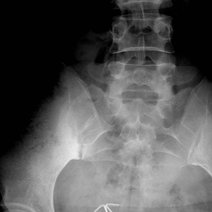

- 强直性脊柱炎,是一种慢性炎性疾病,主要侵犯骶髂关节、脊柱骨突、脊柱旁软组织及外周关节,并可伴发关节外表现。临床主要表现为腰、背、颈、臀、髋部疼痛以及关节肿痛,严重者可发生脊柱畸形和关节强直。西医学名强直性脊柱炎英文名称,所属科室内科免疫内科

- 强直性脊柱炎强直性脊柱炎(AS)是以骶髂关节和脊柱附着点炎症为主要症状的疾病。强直性脊柱炎属风湿病范畴,病因尚不明确,是以脊柱为主要病变部位的慢性病,累及骶髂关节,引起脊柱强直和纤维化

- 强直性脊柱炎强直性脊柱炎是指主要累及双侧骶髂关节、脊柱关节、外周关节和关节周围组织的一种系统炎症性疾病。临床上常见以休息时下腰部(或腰背部)、髋关节或下肢多个大关节疼痛为主要表现。